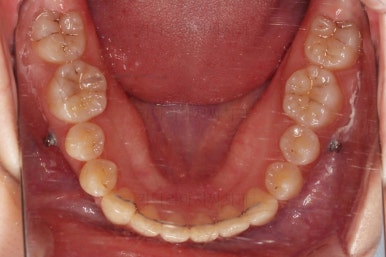

입 안을 보면 밑에 치열이나 다른 부분은 비교적 양호한데 유달리 윗니 송곳니만 위치가 좋지 못하네요.

충치가 곳곳에 보이는데요.

성인들은 충치가 멈춰있는 정지우식일 가능성도 있으며 크기가 현재 크지 않고 향후 변화되지 않는다면 그대로 두기도 합니다.

이번 환자분도 교정치료에 방해되는 부분이나 급해보이는 추료만 우선 진행하고 교정 중에 충치가 커지는지 증상이 생기는지 관찰해 보기로 했습니다.